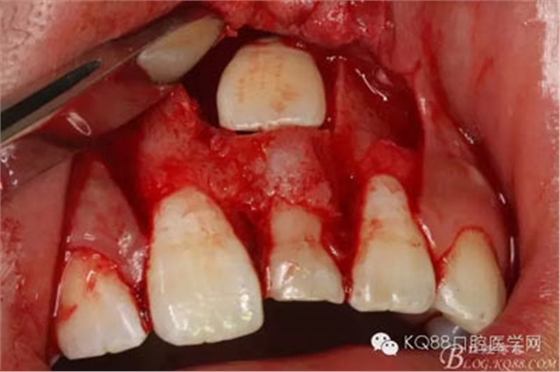

圖16.牙冠上方覆蓋膠原蛋白膜

圖17.骨壁重新覆蓋回去

圖18.縫合

圖19.摘除的牙瘤和囊壁組織